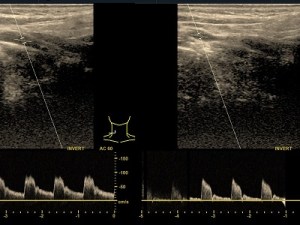

Doppler tętnic szyjnych

Badanie wykonywane jako przesiewowe do wykrywania małych zmian miażdżycowych i czynników ryzyka choroby wieńcowej. Wykonywane też z powodu zawrotów głowy w celu oceny przepływów w tętnicach kręgowych.

Zapis dopplerowski z tętnicy- małe zmiany miażdżycowe.

Doppler tętnic kończyn dolnych

Wykrywa zmiany miażdżycowe i zwężenia oraz niedrożności w tętnicach.

Zapis dopplerowski z tętnicy- duże zmiany miażdżycowe ze zwężeniami.